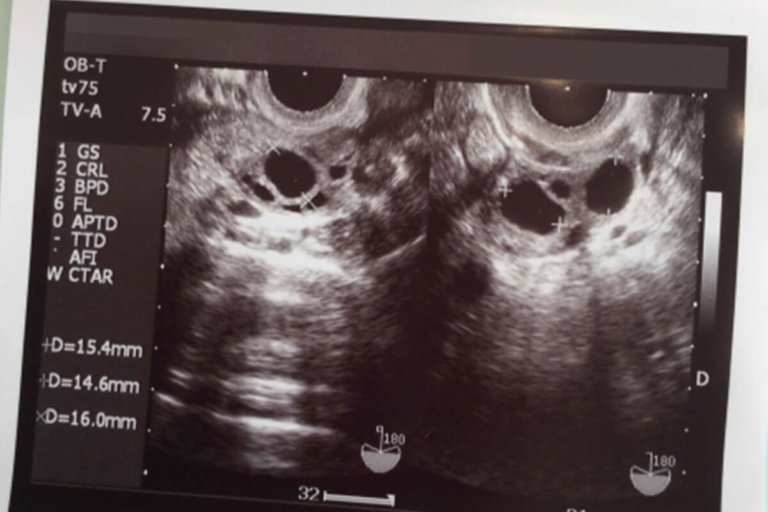

超音波プローブを膣に挿入する経膣超音波検査を受けることもあります。

• 経膣超音波検査。内診。超音波プローブを膣内に挿入して卵巣の画像を取得します。

卵巣、子宮頸部、周囲の臓器や組織の詳細な画像を作成するために超音波スキャンが必要になる場合もあります。これは、腹部超音波スキャンまたは経膣スキャンである場合があります。場合によっては、両方を兼ね備えている人もいます。